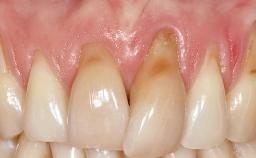

A 30-year-old woman was referred by her general dentist for evaluation of an esthetic complication related to previous implant treatment for congenitally missing maxillary lateral incisors. The patient’s chief complaint was the inadequate esthetic appearance of her smile. The case demonstrates the use of a combined approach to achieve optimal results. Two different flap designs - a tunnel technique and a coronally advanced flap - are employed based on the surgical objectives for the affected site.

Periodontal Plastic Surgery and Prosthetic Procedures to Treat Peri-Implant Soft-Tissue Dehiscences